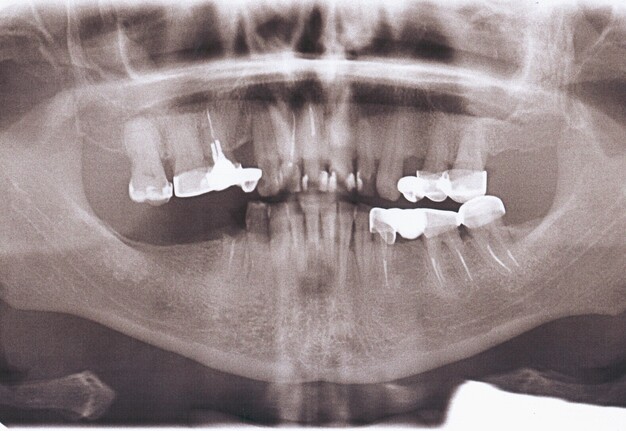

Orthopantomography (Fig 2) showed a minor area of ​​alveolar ridge resorption in the area between the lower left lateral incisor and canine.